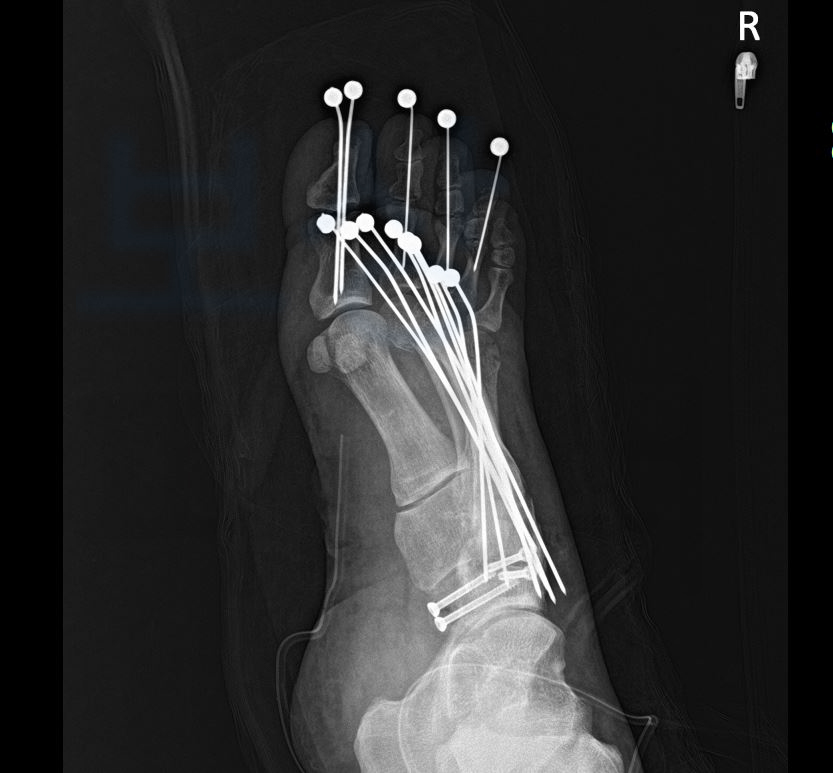

다발성 발가락 압궤손상으로 1 ~ 5번 족지 모두 금속으로 고정하는 수술을 받으셨어야 했습니다.

위 인정된 상병명을 보시면 **우측 2~5족지 개방성 골절 **및 발등의 골절 모두 인정받았죠. 산재 신청이 무사히 완료된 의뢰인은 휴업급여도 지급받으시며 산재 요양을 받게 되었는데요, 안타깝게도 엄지 발가락의 골절 부위에 골수염이 발생하여